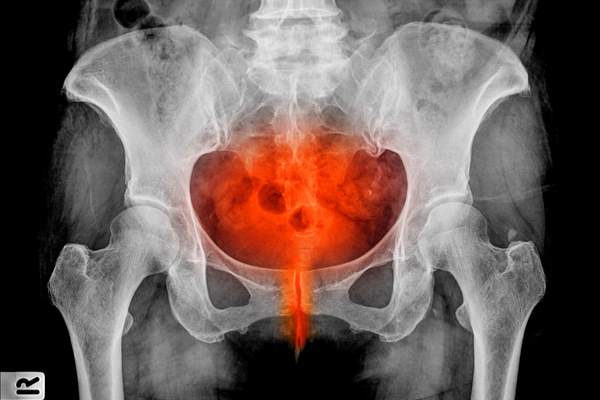

There cystitis it’s an annoying irritation of the bladder mucosa that primarily impacts the girls, inflicting a relentless and somewhat painful must urinate. An additional criticality is the truth that, if uncared for, it’s a sort of drawback that may recur cyclically and grow to be poweri, additionally extending to the genital and higher urinary tracts.

The causes there are numerous: usually it is because of a weakening of the immune system, different occasions to the consumption of sure medicine or incorrect hygiene. Signs related to it are painful with intense sensation of urination, problem, bleeding, burning. Many are the pure treatments to combat it: let’s have a look at what they’re and what to eat in case of cystitis.